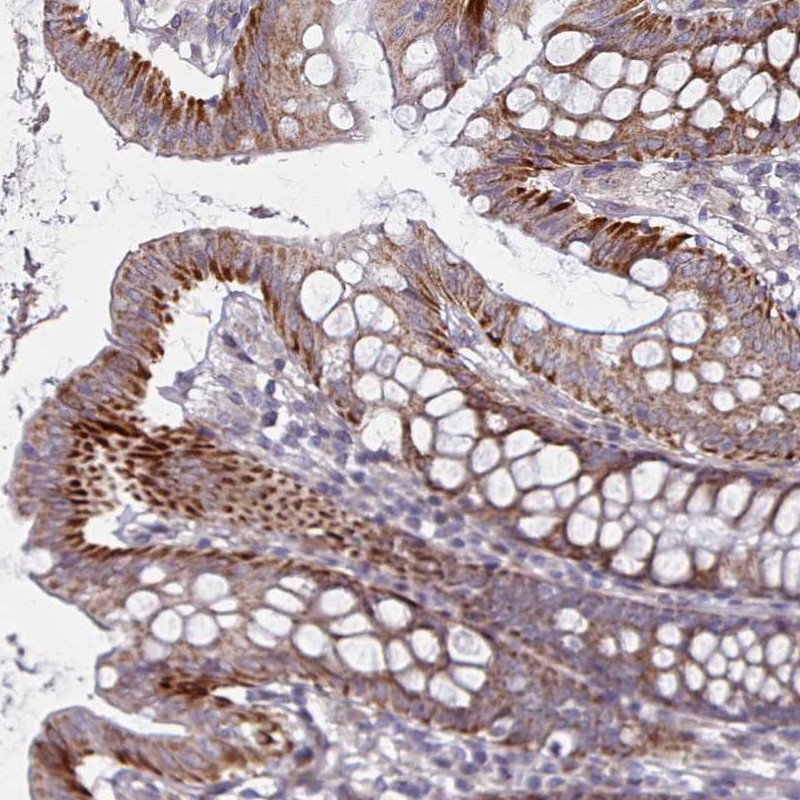

Immunohistochemical staining of human colon shows strong cytoplasmic positivity in glandular cells.